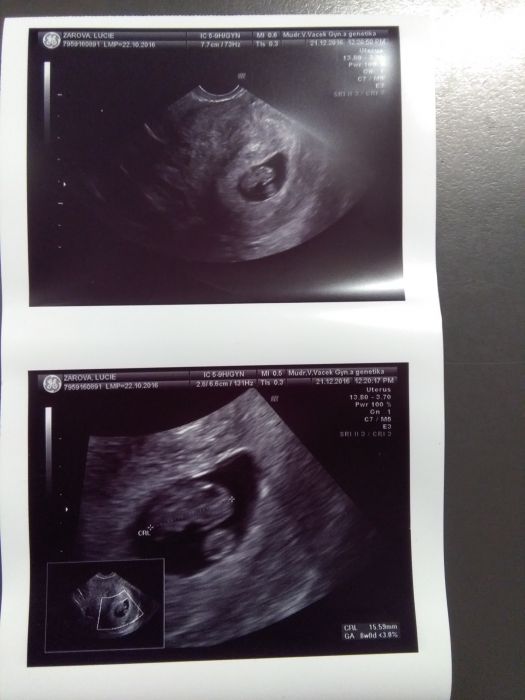

Presne jak pise Ajka, chapeme ze testujes, ja taky testila jako o zivot :-) kontrola dnes ok, jsem 8+4, dle utz 8+0 mimi ma skoro 16mm, doktor mi postil i srdicko, takze jsem ho nejen videla tlouct ale i slysela :-) mam nove fotecky :-) dalsi kontrola 11.1 :-)